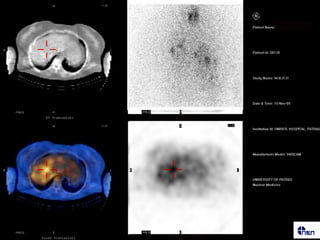

• 71.

27 αζζεκείξ μεαζαθή εονήμαηα ζε CT, AVS

• 72.

131I-Norchol Πνόζζηα 3 Ημένεξ Οπίζζηα ???? Πνςημπαζήξ οπεναιδμζηενμκηζμόξ

• 73.

SPECT/CT IHA Transverse